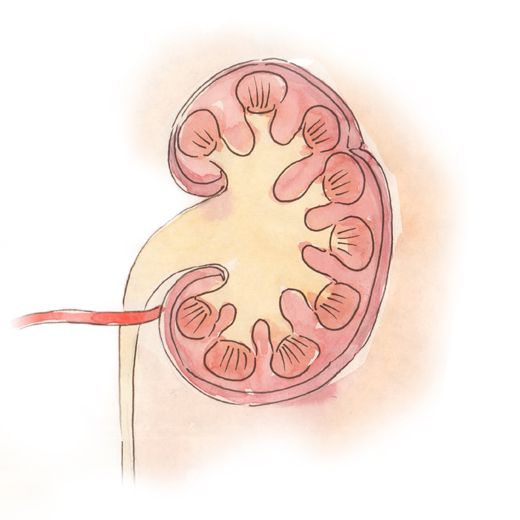

Интраренальная лоханка: рентгеновские снимки и примеры